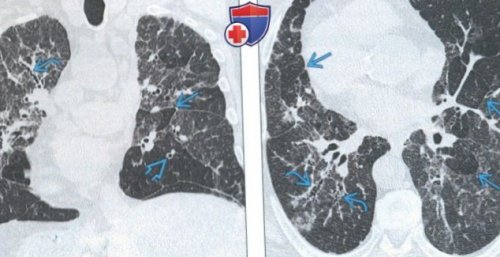

«ловушками». Была выполнена криобиопсия, подтвердился перибронхиальный интерстициальный

интерстициальным фиброзом. Обратите внимание на

перибронхиальном интерстициальном фиброзе:наряду с тракционными (Слева) На аксиальной КТ • Характерные патологические изменения:

(Слева) На аксиальной КТВР • Распределение:— Воздушные «ловушки»: